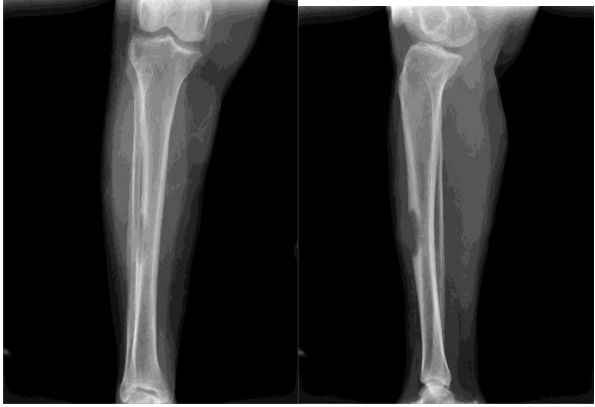

CASE 54: Risk of fracture due to metastasis of tibia (shinbone) from uterine (endometrial) cancer.

Before the surgery: X-ray shows a risk of fracture due to damage and destruction in the middle portion of the tibia.